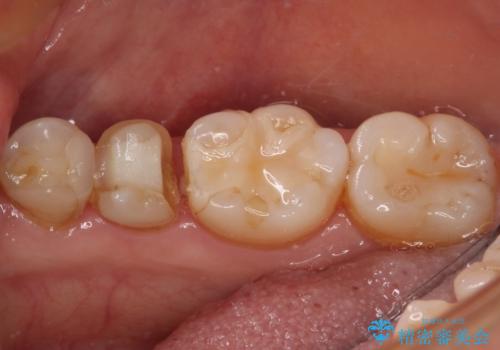

- 他院にて治療した詰め物が欠けてしまった事を主訴に来院された患者様です。

詰め物の範囲が大きく、部分的な詰め物では再び割れてしまうリスクが高いため、

オールセラミッククラウンにて補綴することとしました。